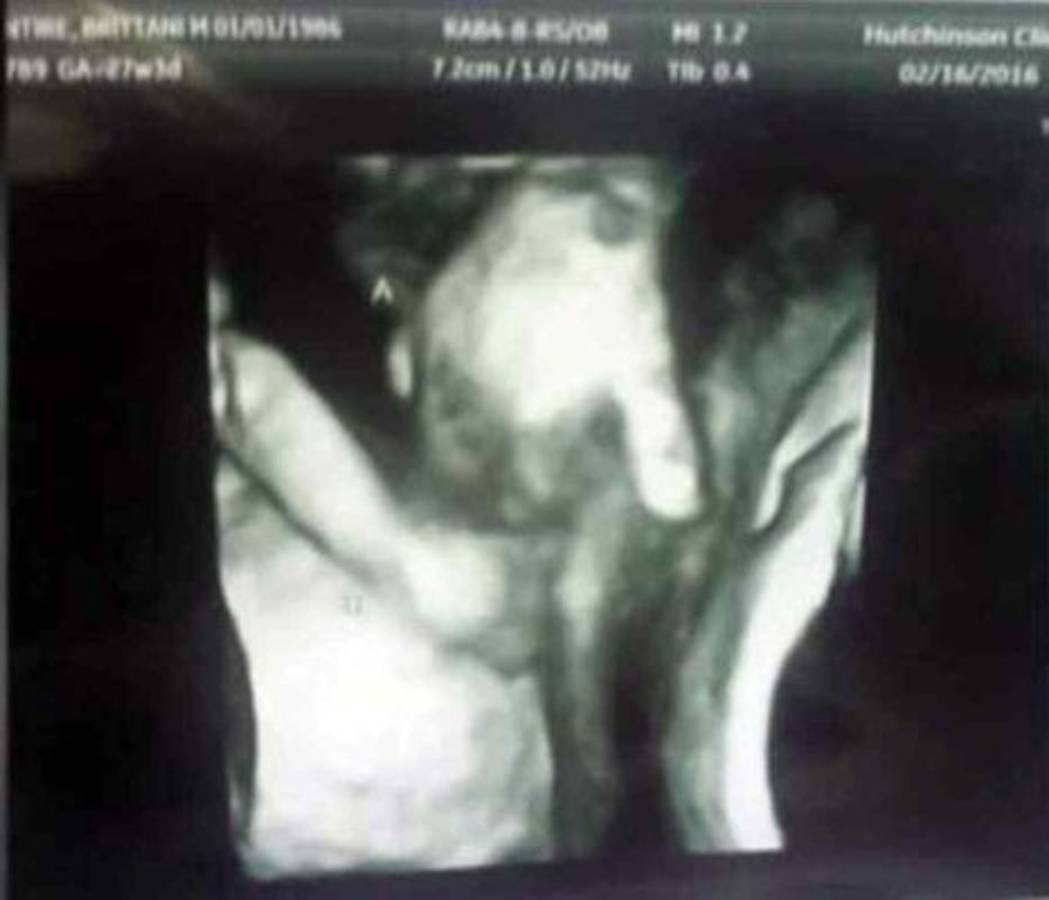

Medios de comunicación en diferentes partes del mundo han compartido la imagen e historia de los hijos de Brittani Mclntire y su marido, gemelos que aparecen tomados de la mano en un ultrasonido.

La foto es realmente conmovedora no solo por el acto de amor entre los hermanos si no porque uno de los bebés tiene probabilidades de no sobrevivir tras su nacimiento, ya que tiene un agujero en el corazón y problemas en con su cerebro.

La madre de las criaturas Mclntire, dijo a la cadena local de noticias ABC6:‘‘Es agradable descubrir lo que se ve en la imagen. Yo los llevo dentro de mi y me gustaría estar con él (su hijo que tiene pocas probabilidades de sobrevivir), pero su hermanita es la única que puede estar ahí, cerca, y nos reconforta saber que si él muere, no estuvo solo en ningún momento’’.

El ultrasonido fue tomado en la sexta semana de embarazo, fue ahí cuando se dio a conocer que el gemelo varón Mason tiene esas complicaciones.